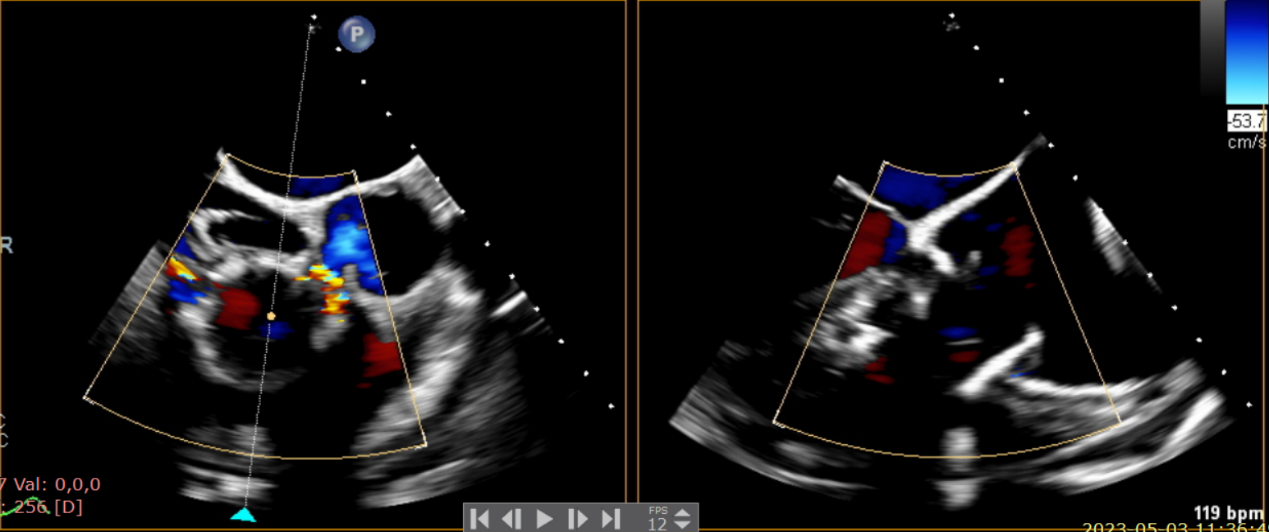

術(shù)中輸送器在超聲引導(dǎo)下調(diào)整位置

術(shù)后Azeem Latib教授對LuX-Valve Plus經(jīng)血管三尖瓣置換系統(tǒng)的器械性能和治療效果大為稱贊,并且認(rèn)為LuX-Valve Plus的手術(shù)體驗非常好。從治療效果來看,術(shù)后即刻超聲顯示三尖瓣反流幾乎完全消失,血流動力學(xué)改善顯著,患者恢復(fù)快。在面對復(fù)雜解剖結(jié)構(gòu)、超聲影像質(zhì)量不佳、有起搏導(dǎo)線干擾時,Lux-Valve Plus也體現(xiàn)了極強的適應(yīng)性。Thomas Modine教授參與了術(shù)中指導(dǎo),他同樣再次肯定了LuX-Valve Plus術(shù)中操作的便捷性,認(rèn)為LuX-Valve Plus容錯率高,對術(shù)中影像的依賴小,并表達(dá)了后期希望可以更多地應(yīng)用LuX-Valve Plus三尖瓣置換系統(tǒng)于臨床實踐,讓更多的三尖瓣重度反流患者盡早獲益,改善預(yù)后。